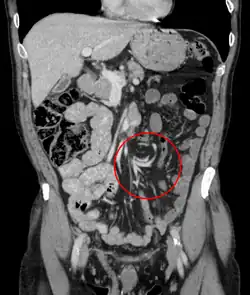

Coronal CT of the abdomen, demonstrating a volvulus as indicated by twisting of the bowel stock | |

Coronal view of sigmoid volvulus with "whirlpool sign"